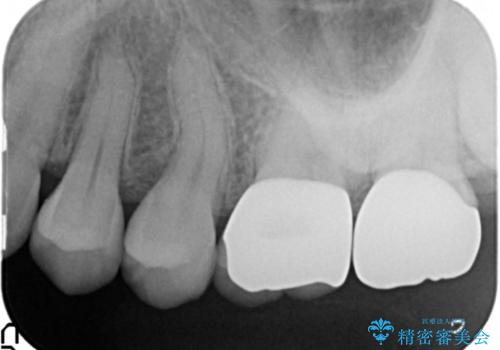

銀歯をジルコニアクラウンで置き換えることで、口腔内が明るく審美的な状態に置き換えることができました。